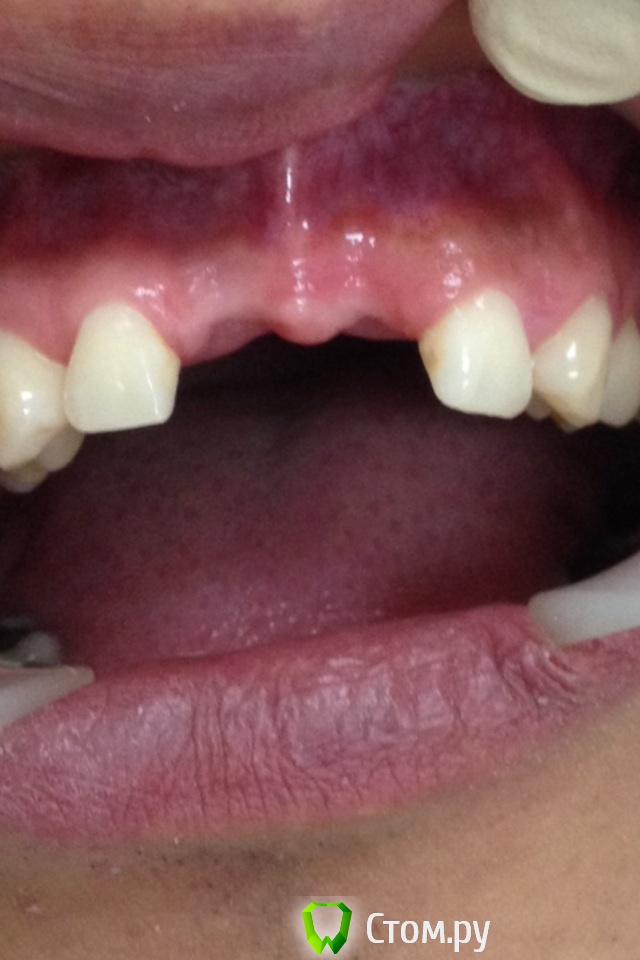

Chewey Опубликовано 23 июля, 2014 Поделиться Опубликовано 23 июля, 2014 (изменено) Какие варианты можно предложить ? Пациент 32 года, потерял 11,21. В следствии травмы, по высоте все неплохо, а вот объем в области 11. 2,6 мм , а в области 21,. 4.3мм. Изменено 23 июля, 2014 пользователем Chewey Ссылка на комментарий

Chewey Опубликовано 23 июля, 2014 Автор Поделиться Опубликовано 23 июля, 2014 Выложите фото.Любой каркасный способ подойдетОбновил Ссылка на комментарий